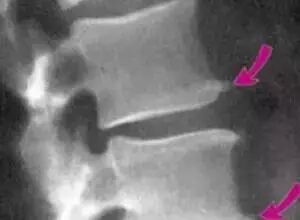

我们俗称的骨质增生或者骨刺,也就是医学术语里的“骨赘”,常见于中老年人群,多形成于骨骼的边缘,呈新生的骨组织,在 X 光片上呈现底部宽、*细的突起样表现。在一些患者身上会出现疼痛等症状。

只有当骨赘压迫到神经、血管并引发病理症状,如肢体出现严重的疼痛麻木、影响相应关节功能的时候,会考虑手术治疗,手术主要的方法是切除骨赘,解除骨赘对神经或者软组织的刺激,达到缓解疼痛改善功能的目的。